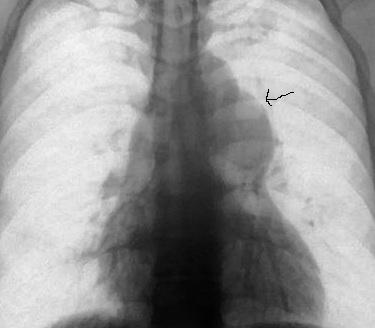

1、两肺纹理稀疏,肺叶透亮度增强。

2、肺动脉段显著膨隆,心影不大。

考虑:肺动脉狭窄?肺动脉瘤?

肺动脉段突出膨隆

纵隔内占位可能性大,建议ct检查.

不支持肺动脉干狭窄,动脉瘤或纵隔占位(良性)